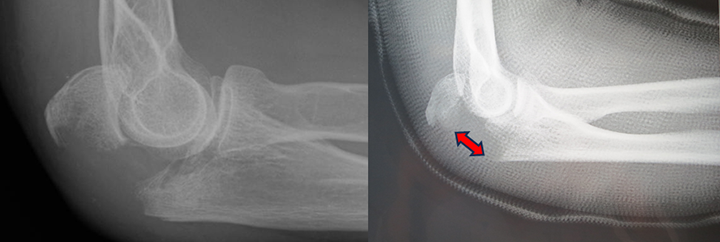

肘頭が骨折すると、そこに付着している上腕三頭筋という上腕の後ろに存在する太い筋腱によって引っ張られ、肘頭がずれてしまいます(図1-a)。そうなりますと、肘の動きが損なわれ、そして肘の当たりが激しく腫れ、押さえると非常に痛みを感じるようになります。

保存療法は、肘頭が骨折しても、折れた骨があまりずれていない場合に行われます。具体的には、上腕(かいな)から前腕部(うで)と手まで、肘を少し曲げた状態で、ギプスなどを用いて固定します。もし過度に肘を曲げてしまうと骨のカケラが引き裂かれ、痛みが強くなるので注意が必要です(図1-b)。ギプスは、一か月程度固定します。そして骨折が治った直後から肘の曲げ伸ばしのリハビリテーションを行います。

図1 a: 受傷時の肘頭骨折。折れた骨のかけらが引き裂かれている。

b: 固定の際、肘関節を過度の曲げると骨折した骨のかけらが引き裂かれる。